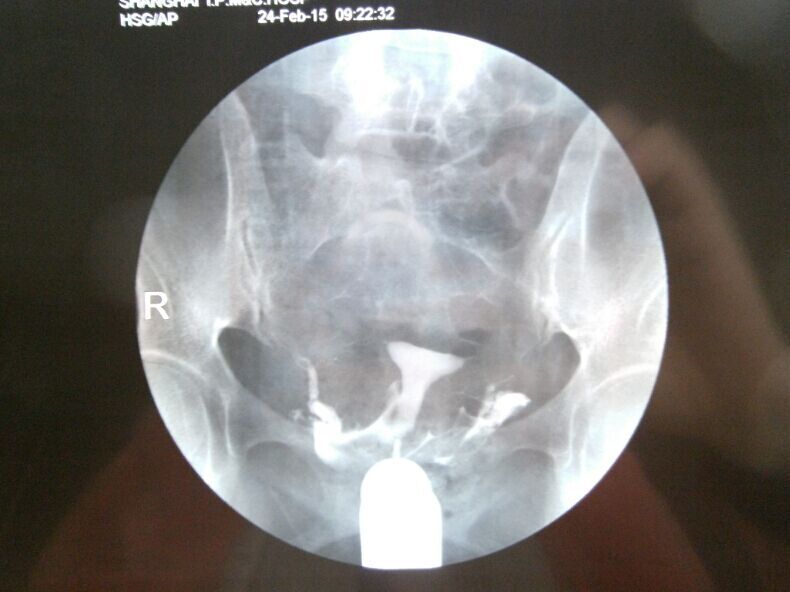

双侧输卵管通而不畅选择哪种治疗方案,谢谢 1、结婚1年多没有做避孕措施;2、我88年,我老公87年,老公检查没什么问题;我做常规检查都正常,在当地三甲医院做过B超(见上传图片),做过6项雌激素(见上传照片);3、量基础体温有排卵,但是拿大卫测试纸却不显示排卵。做过一段时间中药还是没怀孕,现在不知道下一步怎么办?求得解决,谢谢…… 造影报告写着:放射学表现:盆腔平片:盆腔内未见异常密度影。注入造影剂后即刻盆腔摄片:宫腔大小形态正常,腔壁光整。双侧输卵管显影,形态柔软。20分钟后复查摄片:盆腔内见造影剂均匀涂抹,双侧输卵管内少量造影剂残留。放射学诊断:子宫腔正常,双侧输卵管通而不畅。 点击展开 匿名用户 2015-03-06 21:29 为您推荐: 其他回答 你好,联系下次月经过后3-7天内可以去做个输卵管通液,一般是有效果的 天使7737 2015-03-06 23:07 相关问题 您好,我现在双侧输卵管通而不畅,我想治疗,有什么方法吗? 双侧输卵管通而不畅有哪些治疗方案 有没有懂中医的人,帮我看看这个方子和这个治疗方案,谢谢 我是通过造影查出双侧输卵管通而不畅

1、结婚1年多没有做避孕措施;2、我88年,我老公87年,老公检查没什么问题;我做常规检查都正常,在当地三甲医院做过B超(见上传图片),做过6项雌激素(见上传照片);3、量基础体温有排卵,但是拿大卫测试纸却不显示排卵。做过一段时间中药还是没怀孕,现在不知道下一步怎么办?求得解决,谢谢…… 造影报告写着:放射学表现:盆腔平片:盆腔内未见异常密度影。注入造影剂后即刻盆腔摄片:宫腔大小形态正常,腔壁光整。双侧输卵管显影,形态柔软。20分钟后复查摄片:盆腔内见造影剂均匀涂抹,双侧输卵管内少量造影剂残留。放射学诊断:子宫腔正常,双侧输卵管通而不畅。